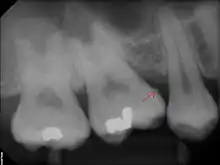

Sub-gingival calculus formation and chemical dissolution

Sub-gingival calculus is composed almost entirely of two components: fossilized anaerobic bacteria whose biological composition has been replaced by calcium phosphate salts, and calcium phosphate salts that have joined the fossilized bacteria in calculus formations.[37][38] The initial attachment mechanism and the development of mature calculus formations are based on electrical charge.[39] Unlike calcium phosphate, the primary component of teeth, calcium phosphate salts exist as electrically unstable ions. The following minerals are detectable in calculus by X-ray diffraction: brushite (CaHPO4 · 2 H2O), octacalcium phosphate (Ca8H2(PO4)6 · 5 H2O), magnesium-containing whitlockite (Ca9(Mg,Fe)(PO4)6(PO3OH)), and carbonate-containing hydroxyapatite (approximately Ca5(PO4)3OH but containing some carbonate).[40]

The reason fossilized bacteria are initially attracted to one part of the subgingival tooth surface over another is not fully understood; once the first layer is attached, ionized calculus components are naturally attracted to the same places due to electrical charge. The fossilized bacteria pile on top of one another, in a rather haphazard manner. All the while, free-floating ionic components fill in the gaps left by the fossilized bacteria. The resultant hardened structure can be compared to concrete; with the fossilized bacteria playing the role of aggregate, and the smaller calcium phosphate salts being the cement. The once purely electrical association of fossilized bacteria then becomes mechanical, with the introduction of free-floating calcium phosphate salts. The "hardened" calculus formations are at the heart of periodontal disease and treatment.[38]